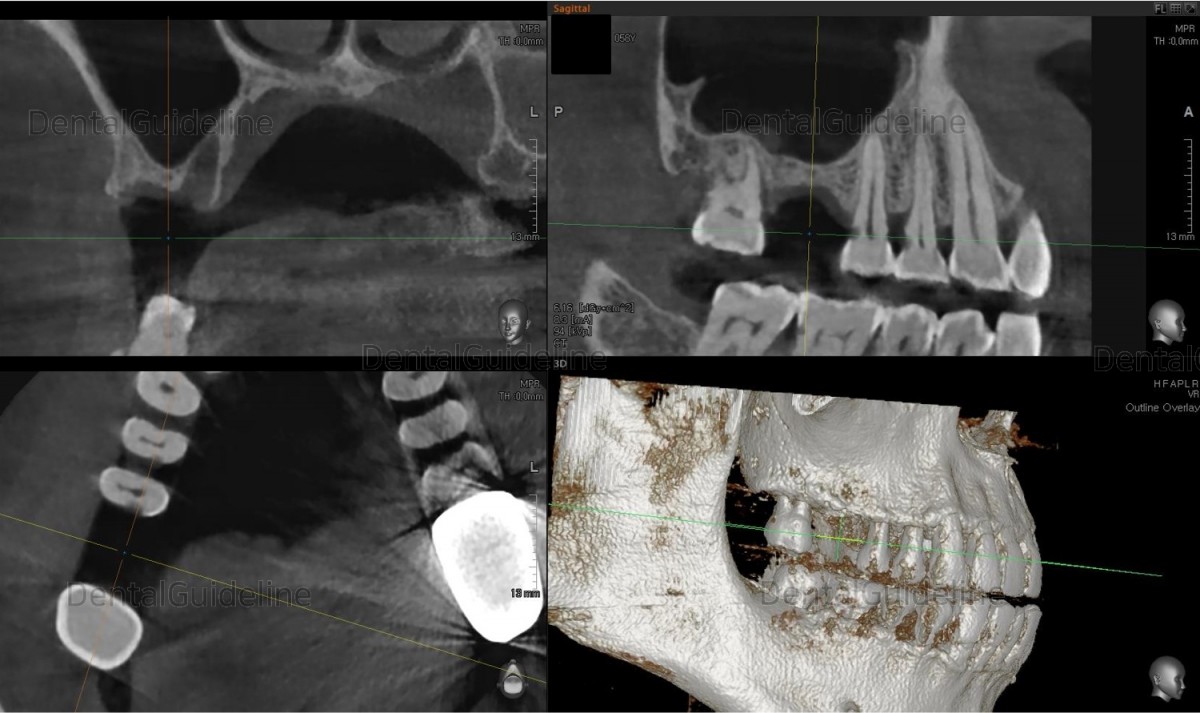

Single implant,Maxillary sinus bone graft & Improved ISQ value, Arum implant system.

A 58-year-old male patient is taking

Baby Aspirin® daily for cardiovascular problems. He also suffered from Behcet's disease. (codeNo. cjkty)

3. Implant placement 4 months after bone graft in the maxillary sinus. ARUM NB1 Ø5/L10mm, 25Ncm. The area was covered with a collagen membrane.

4. CBCT scan immediately after implant placement. ![]()